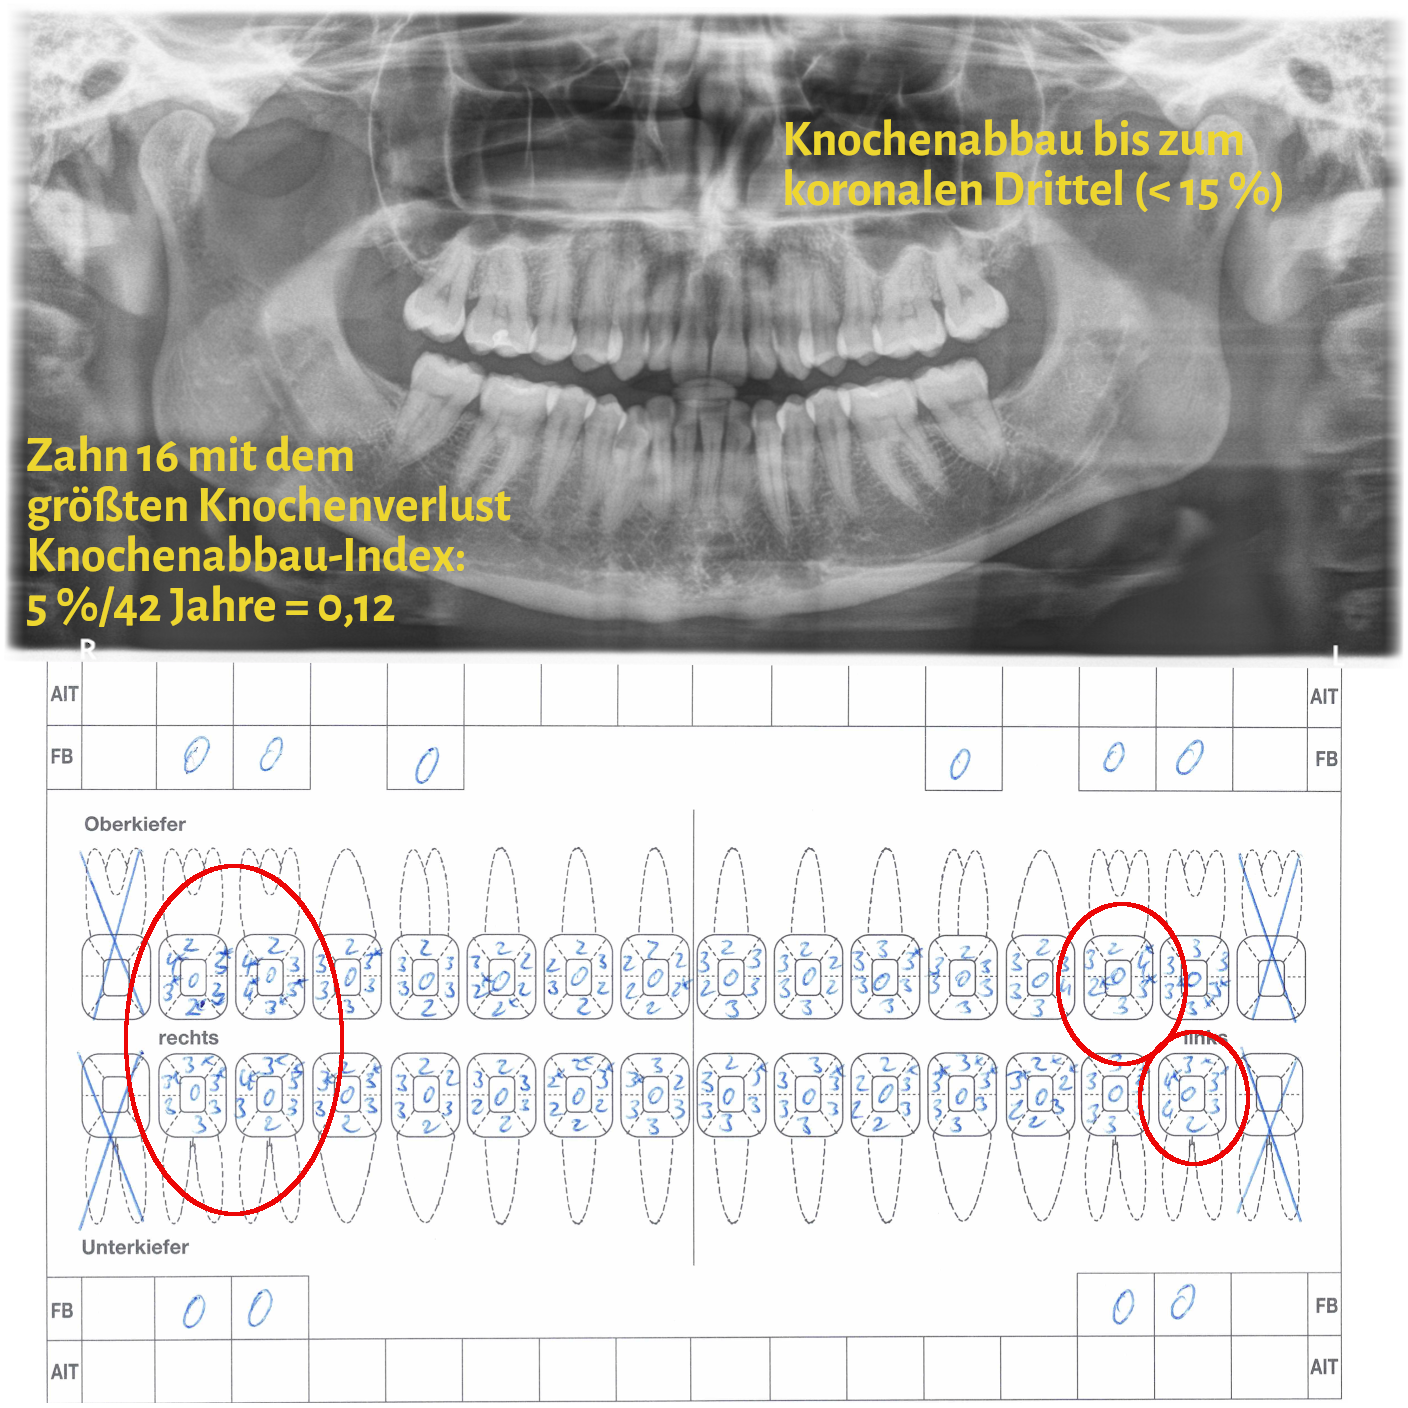

Der Grad enthält Informationen zur Progressionsrate der Erkrankung und dem Vorliegen von patientenspezifischen Risikofaktoren (Nikotinkonsum und Diabetes/HbA1c). Die Progressionsrate kann direkt anhand von Vorbefunden abgeschätzt werden oder indirekt durch den sogenannten Knochenabbauindex (KA %/Alter). Dabei wird der Zahn auf dem Röntgenbild berücksichtigt, der den stärksten marginalen Knochenabbau hat. Das Vorliegen von Risikofaktoren kann zu einem Upgrade führen. Fehlen diese Risikofaktoren, führt das aber nicht zu einem Downgrade.